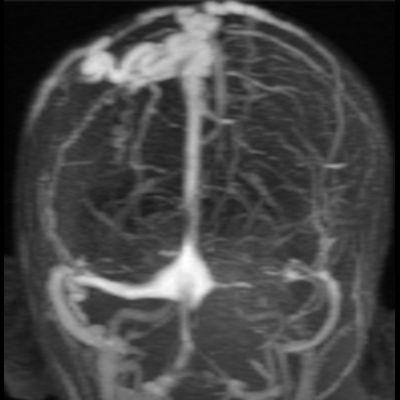

2. B) Kontrastlı MR venografide orta hatta cilt altı dilate (oklar), tortiyoze emisserian vaskuler yapıların superior sagital sinus ile ilişkisi ve devamlılığı (ok) izlenmektedir.